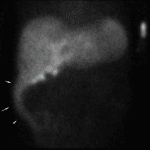

Age: 68

Sex: Male

Indication: Rule out postoperative bile leak, history of TIPS

Radiotracer: Tc99m Mebrofenin

Sample ReportPositive for biliary leak with bile collecting in the right sub-diaphragmatic region and in the right paracolic gutter.